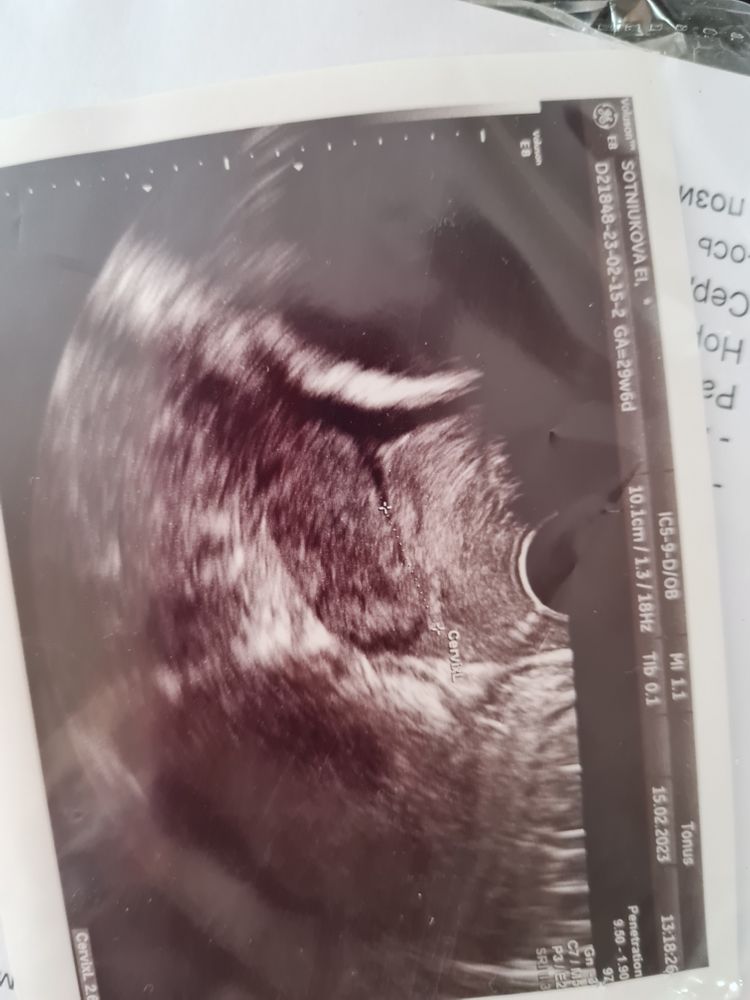

Да ! У меня схлопнулся,да так ,что роды еле вызвали по итогу ,шейка дубоватая была после него .вот фото моего притокрытого зева ,как воронка был Изображение